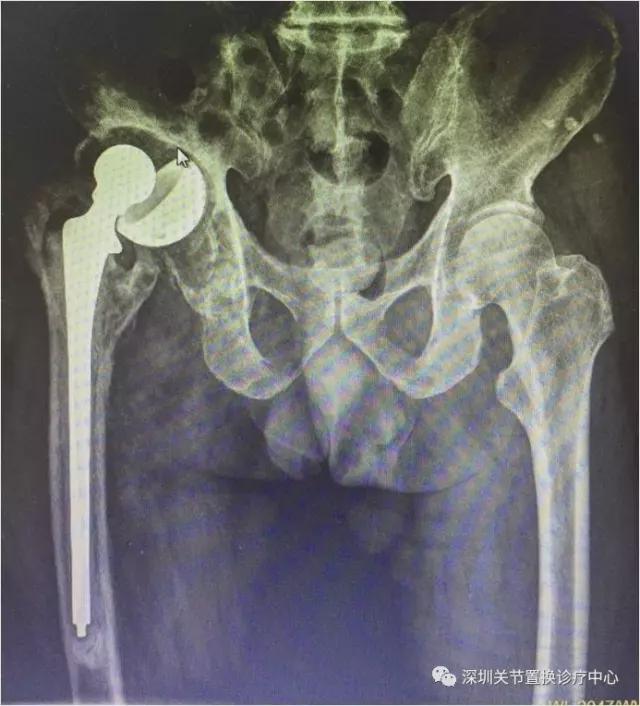

劈开股骨,千辛万苦掏干净骨水泥,取出股骨假体,清理感染组织,放入一个临时的骨水泥假体。

放入临时骨水泥假体的X线片

放入临时假体后患者能做简单的活动,关键是不痛啦!

患侧肢体短缩3cm